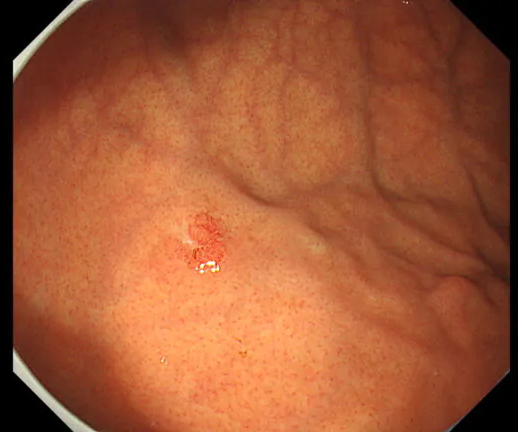

早期食道がん